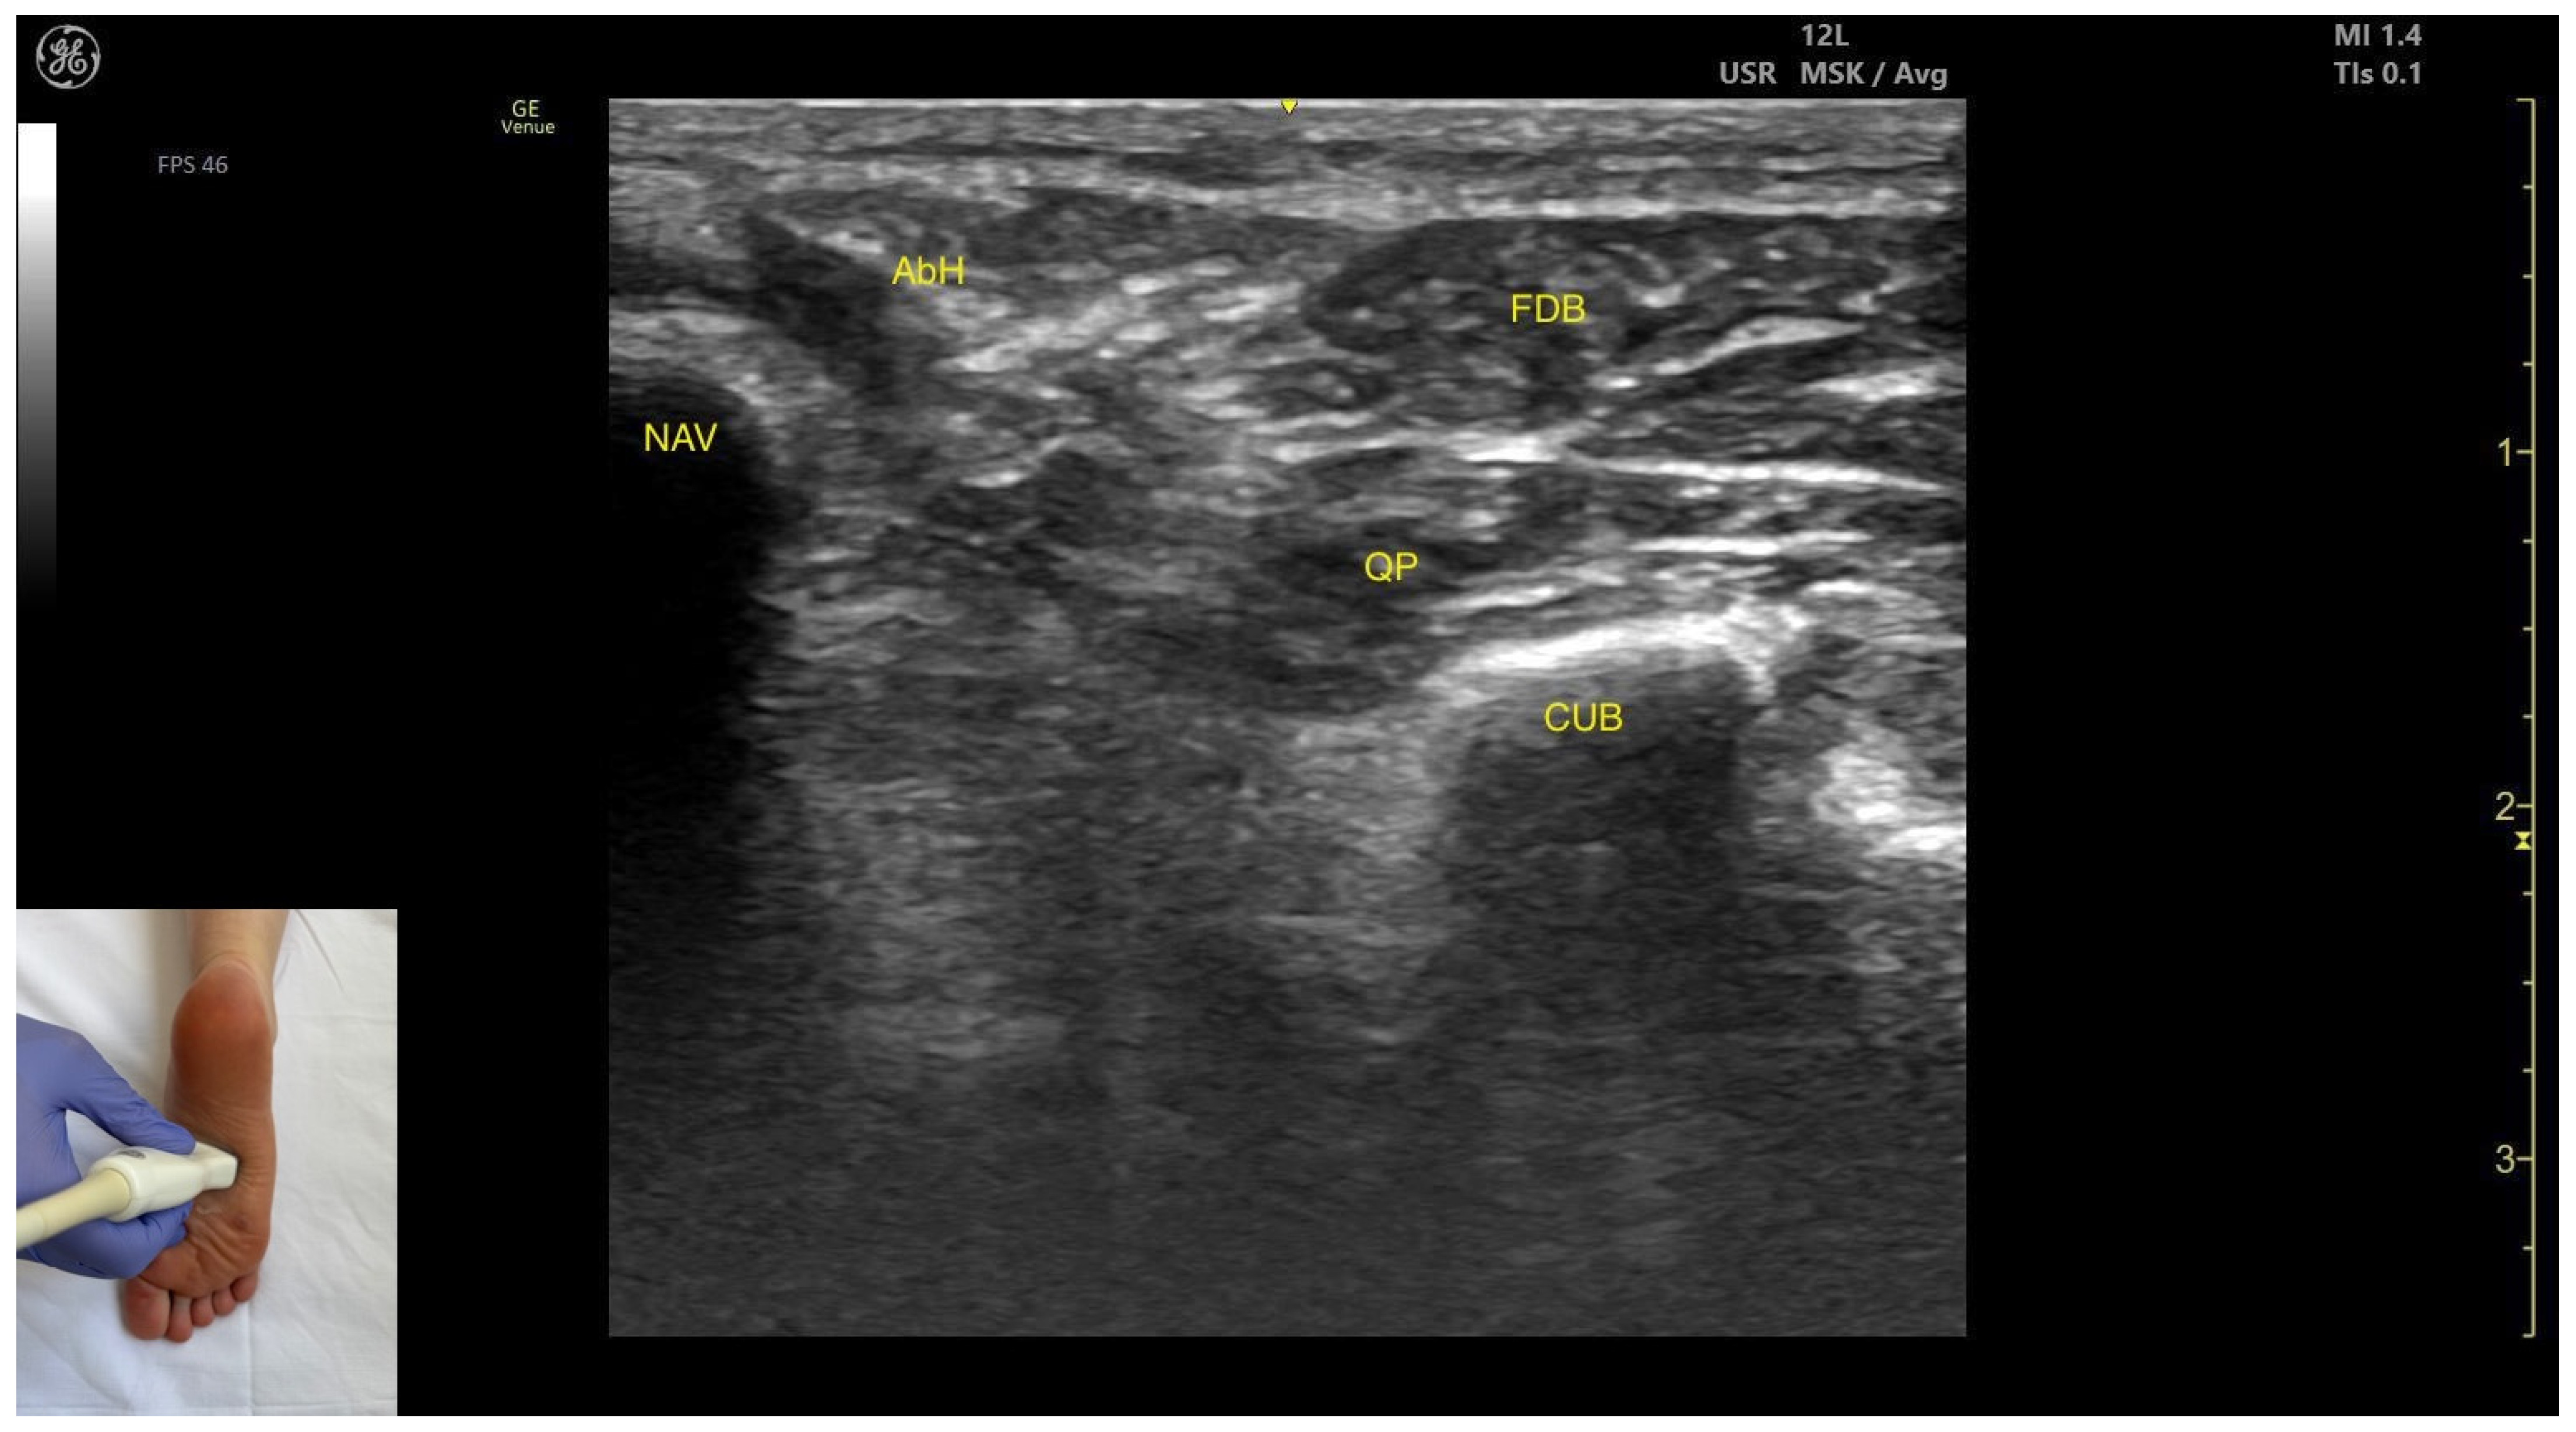

3.8. Flexor Digitorum Brevis (FDB)

3.8.2. Ultrasound Identification

3.8.3. Key Ultrasound Landmarks

- Muscle position: It is a superficial plantar muscle layer. The quadratus plantae is located deep to the FDB. Medial to the FDB and quadratus plantae the abductor hallucis (AbH) is identified.

- External fascia: It features a prominent fascia separating it from the subcutaneous tissue, plantar aponeurosis and from the quadratus plantae, which is important during BoNT-A injection.

- Dynamic evaluation: During dynamic evaluation, scanning toward the calcaneous, a reduction in muscle thickness of the flexor digitorum brevis is observed. Muscle contraction is visible during flexion of toes II–V at the proximal interphalangeal joints (Video S4).

| FDB | Flexor digitorum brevis |

| NAV | Navicular |

| QP | Quadratus plantae |

| CUB | Cuboid |

| AbH | Abductor hallucis |

| Flexor Digitorum Brevis | Mid-plantar aspect of the foot | Plantar aponeurosis (superficial); abductor hallucis (medial); quadratus plantae (deep) | Transverse scan at mid-plantar aspect of the foot | Visualize flexor digitorum brevis as most superficial muscle and confirm muscle position and relations |